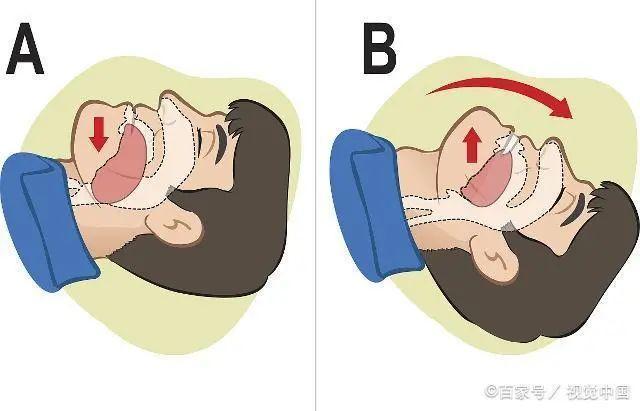

缓慢深呼吸,保持通气

如果患者已经没有自主意识,说明心梗比较严重,此时应该将患者的双臂向上伸直,护住发病患者的颈部,帮助其打开气道,防止患者无法呼吸。

另外,结合人工呼吸的方式来急救,在做呼吸的过程中,需要保持正确,将患者嘴巴,鼻腔的呕吐物或者杂物清理干净。另外,用拇指和食指捏住患者的鼻翼,嘴对嘴往患者的嘴巴吹气,保证有足够的氧气输送,避免患者心梗严重后缺乏氧气而引发不良后果。